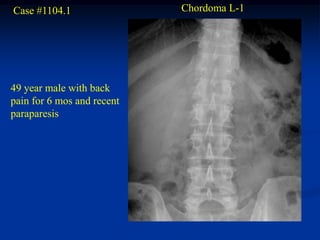

Case #1104.1                Chordoma L-1

49 year male with back

pain for 6 mos and recent

paraparesis